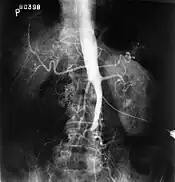

Angiography provides important information regarding the perfusion and patency of distal arteries (e.g. femoral artery). The presence of collateral arteries in the pelvic and groin area is important in maintaining crucial blood flow and lower limb viability. However, angiography should only be used if symptoms warrant surgical intervention.[1]